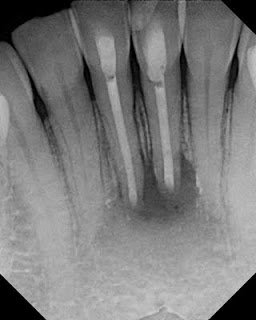

This patient was kicked in the face by a horse in 1998. Teeth were displaced (luxated). She repositioned them herself. RCT’s on #24 and #25 were done in 2008 by her general dentist. In

Jan 2011 she is having pain, percussion sensitivity, normal probings, adjacent teeth WNL. These teeth are diagnosed as: Prior RCT’s w/ Symptomatic Apical Periodontitis.

Axial and sagittal views in CBCT verify that these are single canals incisors. It also shows us the extent of the bone loss prior to our surgical access.

Due to the large size of the canals and over extension of the previous RCT, it was recommended to treat these teeth surgically with an apicoectomy.